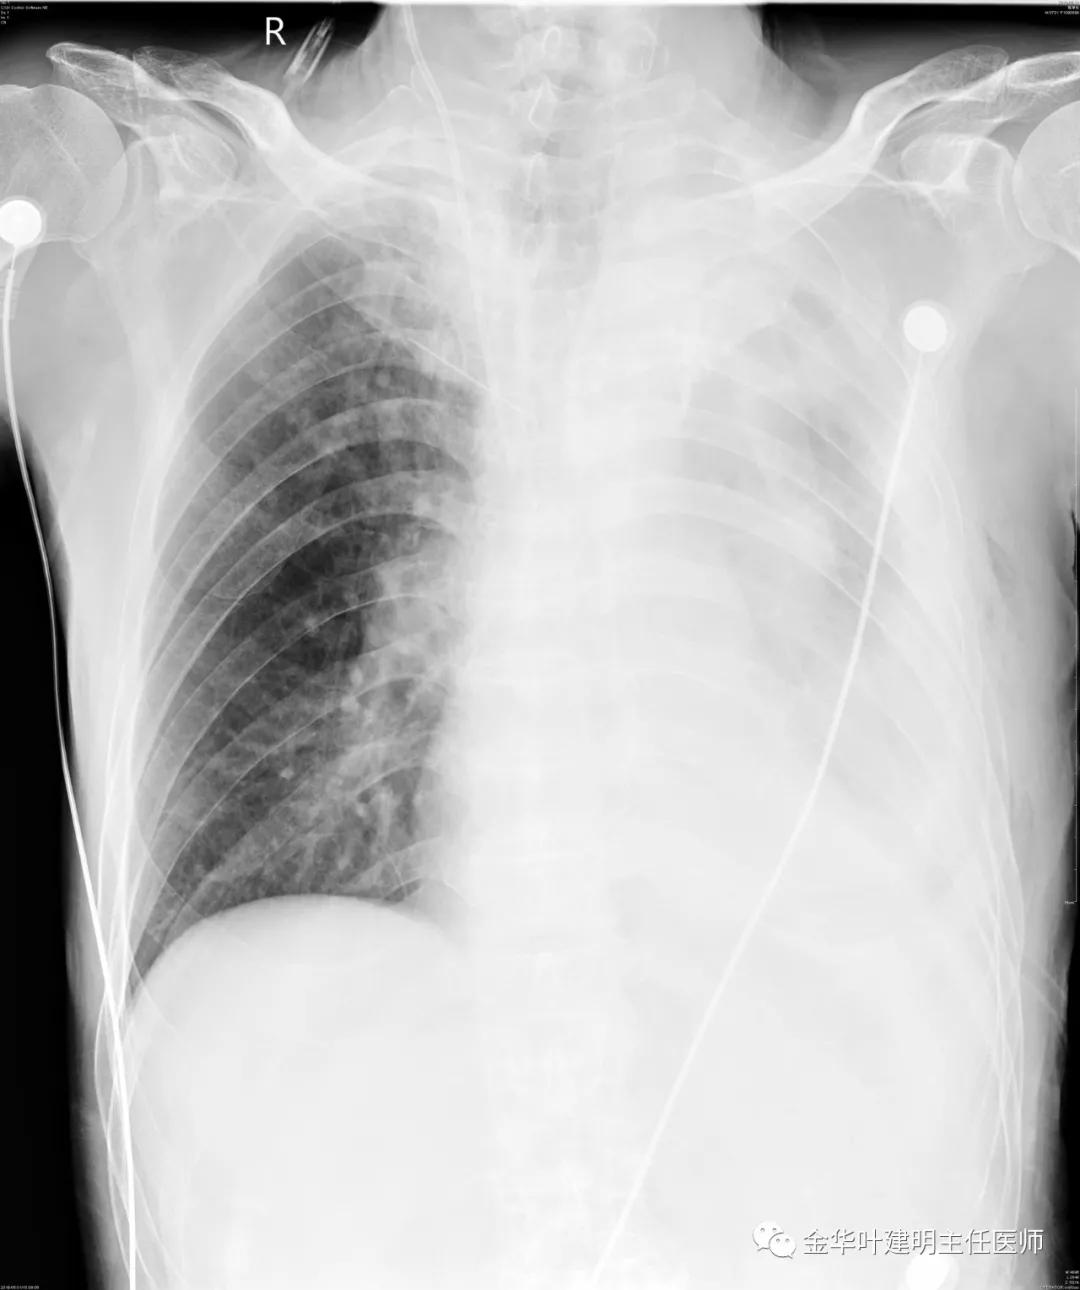

5.31下午7时,从早上开始算胸引700毫升,共900毫升;予以查床边,胸片,结果如下: